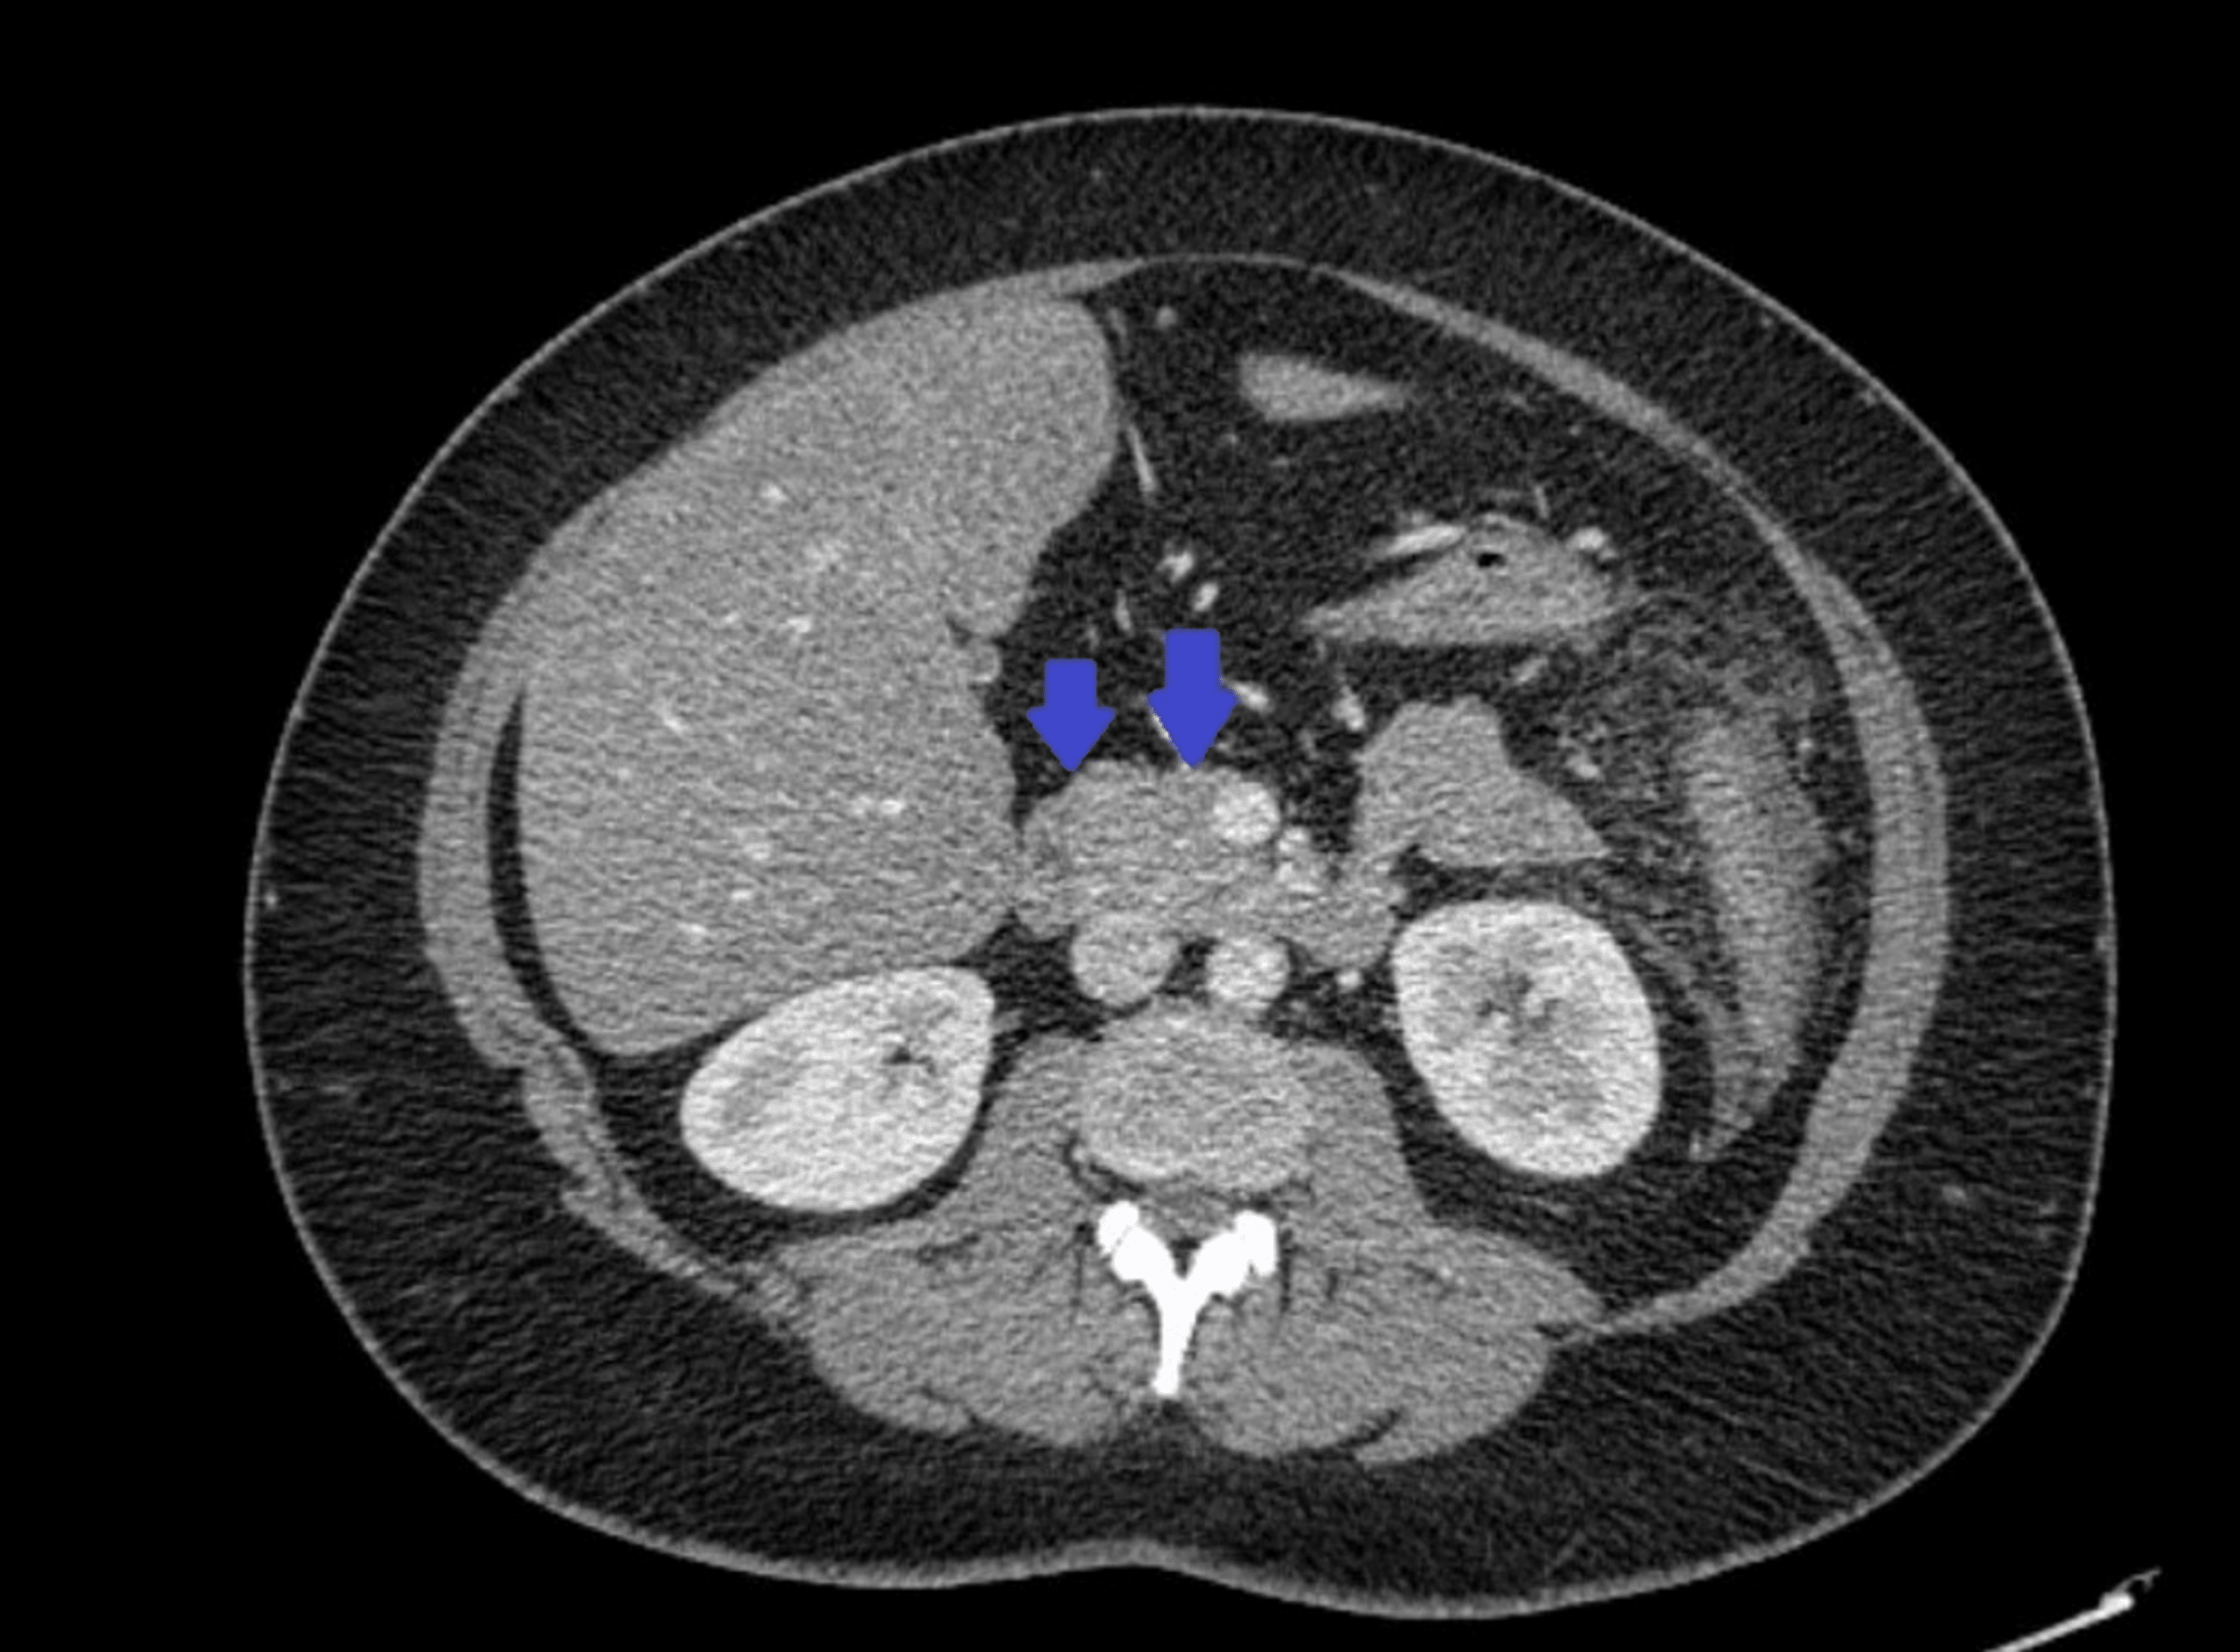

From www.semanticscholar.org

Figure 1 from Acute Pancreatitis After the Use of Belimumab in a Lupus And Pancreatitis gastrointestinal involvement is a common complain observed in. acute pancreatitis may be the first manifestation in systemic lupus erythematosus or occur during evolution. acute pancreatitis is uncommon in systemic lupus. systemic lupus erythematosus (sle) is a complex autoimmune pathology that can involve. Lupus And Pancreatitis.